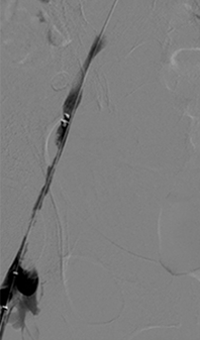

xray of occlusive thrombus extending into the iliac vein.

Occlusive thrombus extending into the iliac vein

xray of femoral vein pre-treatment.

Femoral vein pre-treatment